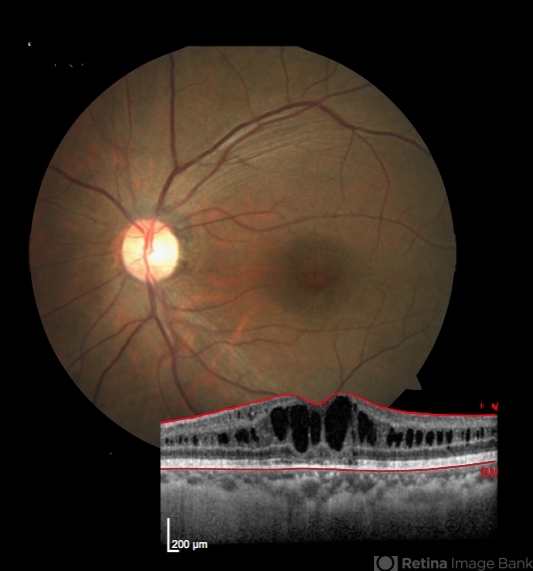

- myopic foveoschisis, cartwheel appearance

- This 37-year-old male presented to us with BCVA of 6/18 . Fundus showed typical cartwheel appearance and was diagnosed with B/L foveoschisis. HRA-OCT was done for documentation which showed typical schitic pattern of fovea . Currently started on dorzolamide eye drops.